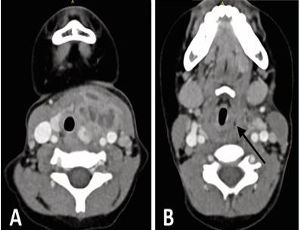

A 3-year-old girl presented with anterior neck swelling near the thyroid gland, slightly left of midline. CT revealed a 2.5 cm deep abscess within the SCM, with a hypodense tract traversing the left thyroid lobe (Figure 1A),and a suspected opening into the pyriform sinus (Figure 1B).

Figure 1 (A) Axial CT showing a left-sided abscess with a hypodense tract traversing the thyroid lobe, medial to major vessels. (B) Suspected internal opening in the left pyriform sinus (arrow).